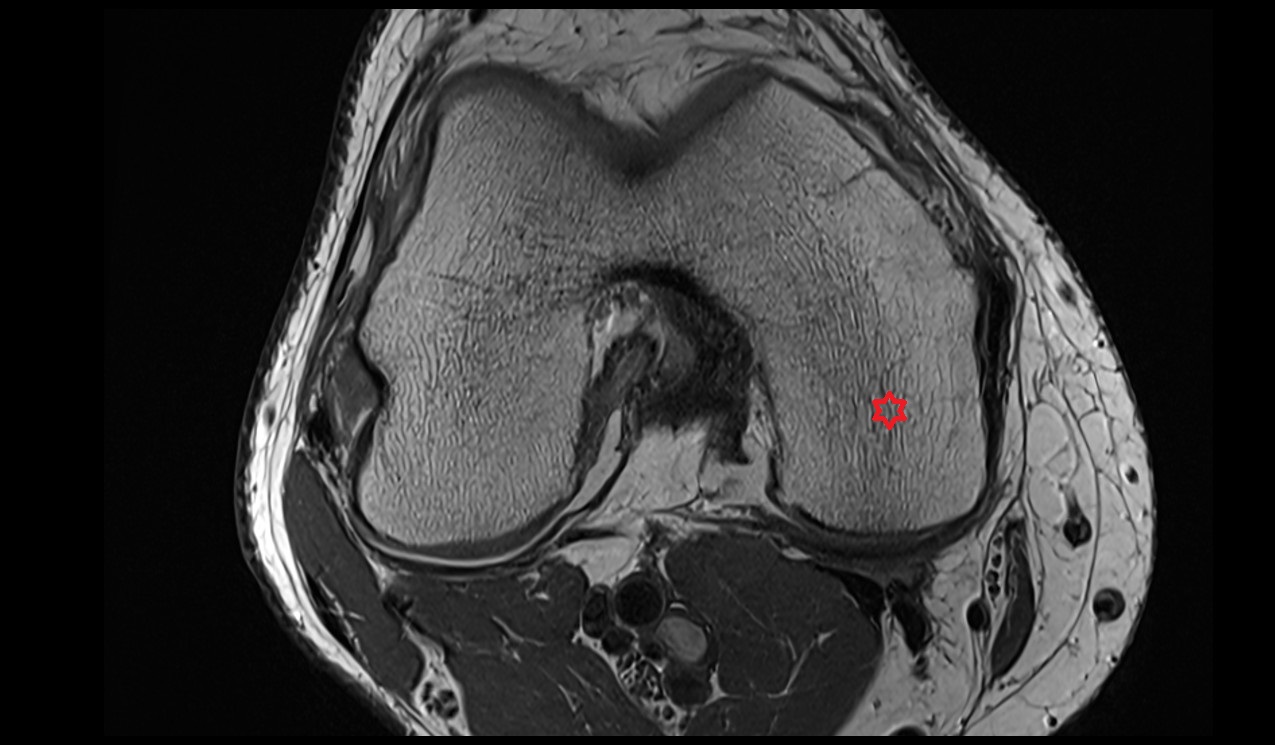

- Lateral condyle of femur

- Medial condyle of femur

- Femoral condyle articular cartilage

- Tibial condyle articular cartilage

- Knee Joint

- Meniscus cartilage

- Lateral meniscus